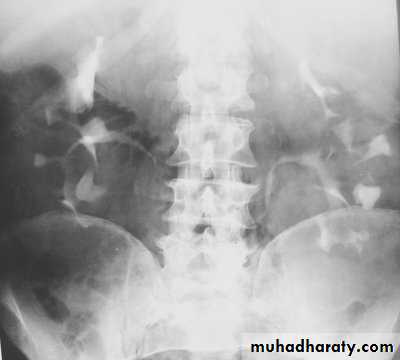

Poly cystic disease

Adult type

Present after the third decade of life , Familial.

Renal parenchyma is replaced by numerous cysts containing fluid , The cysts are of variable size ,

Clinically renal colic, loin mass , heamaturia and hypertension, Renal tissue interposed between the cysts after time dssimcted ended with renal failure

Almost bilateral.

IVU

Large kidney .

Lobulated out-line.

Distortion of pelvi- calyceal system depend on cyst size, number and position.

In advanced cases there is elongation and stretching of minor and major calyces ( spider leg).

In advanced cases IVU shows non-functioning kidney .